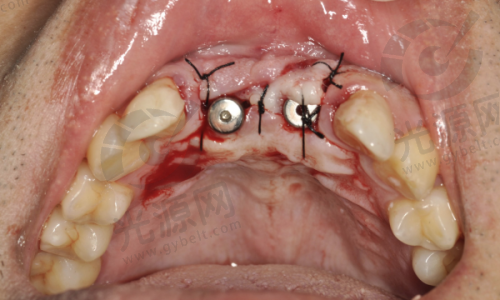

2. 种植牙:依据品牌与材料选择,价格从4599元 - 17000元都有。